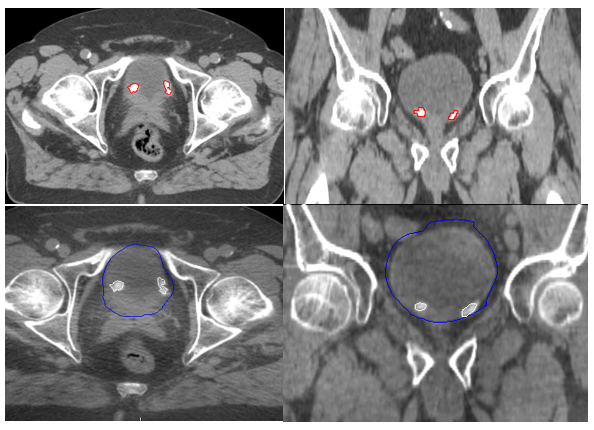

All IH TFM were clearly visible at CT planning and throughout the first 7 - 8 fractions of the partial bladder RT (Fig 2). In addition, there was no significant difference in correlations between the IH TFM visibility and bladder volume. See Table 1.

Figure 2 TraceIT® Blebs at planning CT in axial and coronal views (A and B) and during partial treatment in axial and coronal views (C and D).

In this present study, we have found IH to be a safe and effective TFM for IGRT. IH was found to be straightforward to inject cystoscopically into the bladder submucosa. None of our patients reported any post-operative complications. IH has a comparable tissue density value of 1.02 g/cm3 making it radiopaque on CT and CBCT with each small volume IH TFM clearly visible without any imaging artefacts (Figure 2). However, we were not able to identify the IH TFM on kV imaging. Each IH TFM was successfully injected into the bladder submucosa with no intravesical diffusion, migration or loss seen. The size and shape of the IH TFM remained clearly visible and stable for the entire duration of partial bladder RT with minimal loss of volume (Table 1).